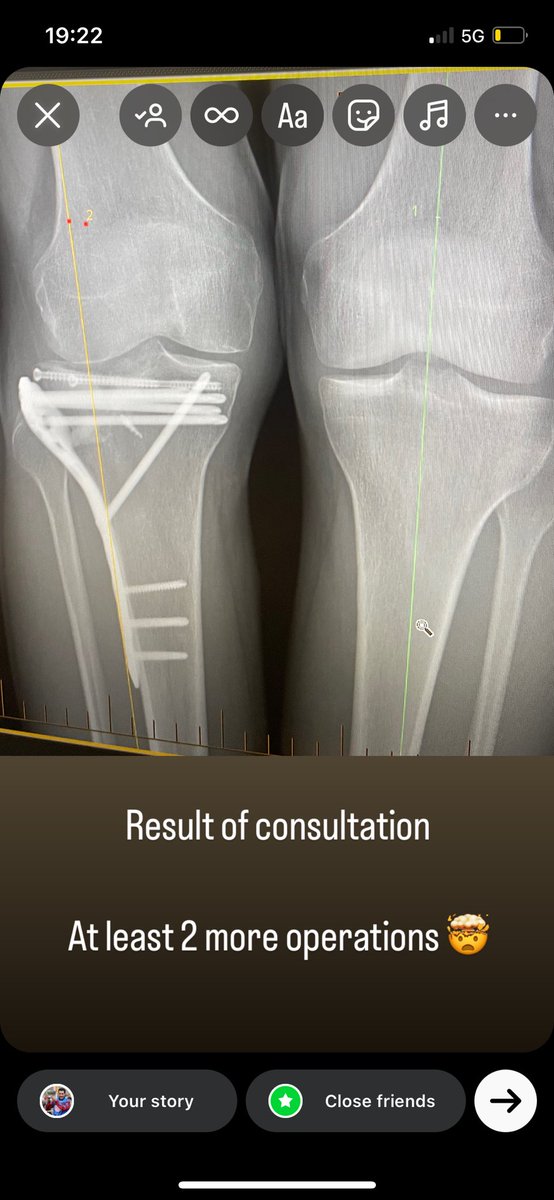

Aidan Coleman@AidanColeman·

Still a long way to go !!

Aidan Coleman tweet media